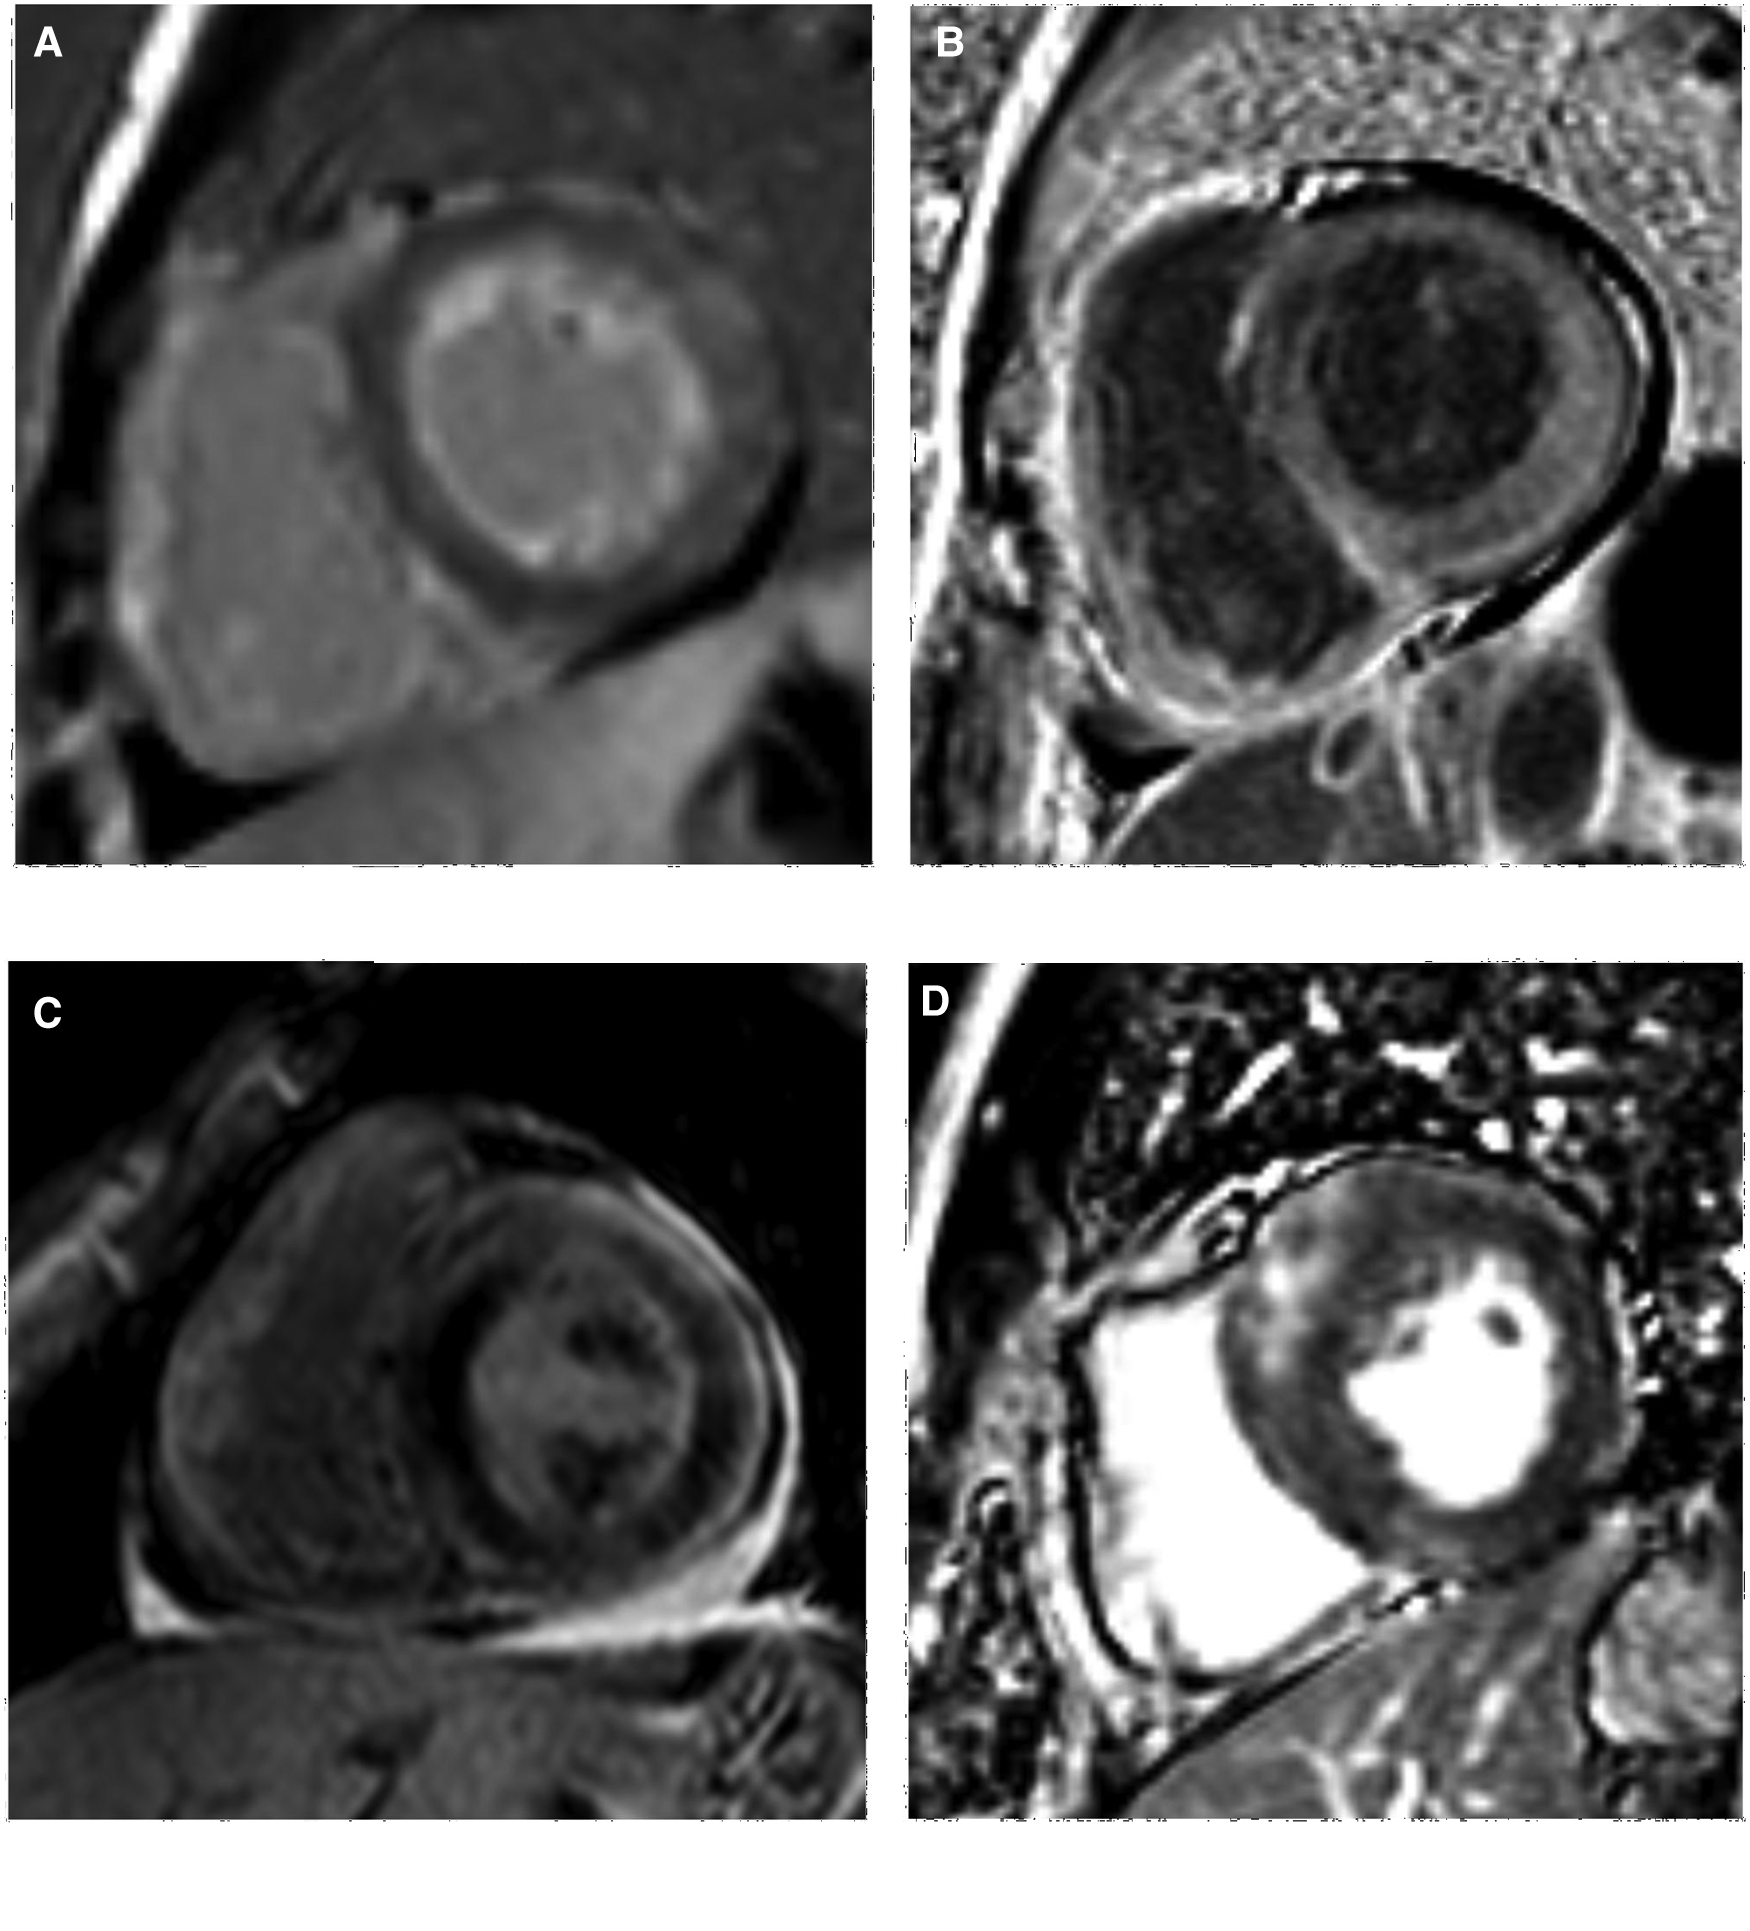

Delayed scanning demonstrated LV myocardial LGE in all the AL-CA patients (30 cases, 100%) with subendocardial, transmural, and focal patchy patterns in 15 (50%), 12 (40%), and 3 (10%) AL-CA patients, respectively (Table 2). Among the 30 HCM patients, 24 (80%) of them showed a focal patchy LGE pattern, but the remaining 6 (20%) did not show any myocardial LGE (Figure 2). These data showed significant differences in the percentages of the three LGE patterns between the AL-CA and HCM patient groups. LV myocardial LGE was not detected in any of the 29 healthy controls. Therefore, LV myocardial LGE patterns of the two patient groups were significantly different compared to the healthy controls (all P < 0.001).

Figure 2

LV LGE images of AL-CA and HCM patients. (A,B) subendocardial and transmural LGE patterns of AL-CA patient, respectively; (C,D) focal patchy LGE pattern of AL-CA and HCM patient, respectively. LV, left ventricular; LGE, late gadolinium enhancement; AL-CA, light-chain patients with cardiac amyloidosis; HCM, hypertrophic cardiomyopathy.